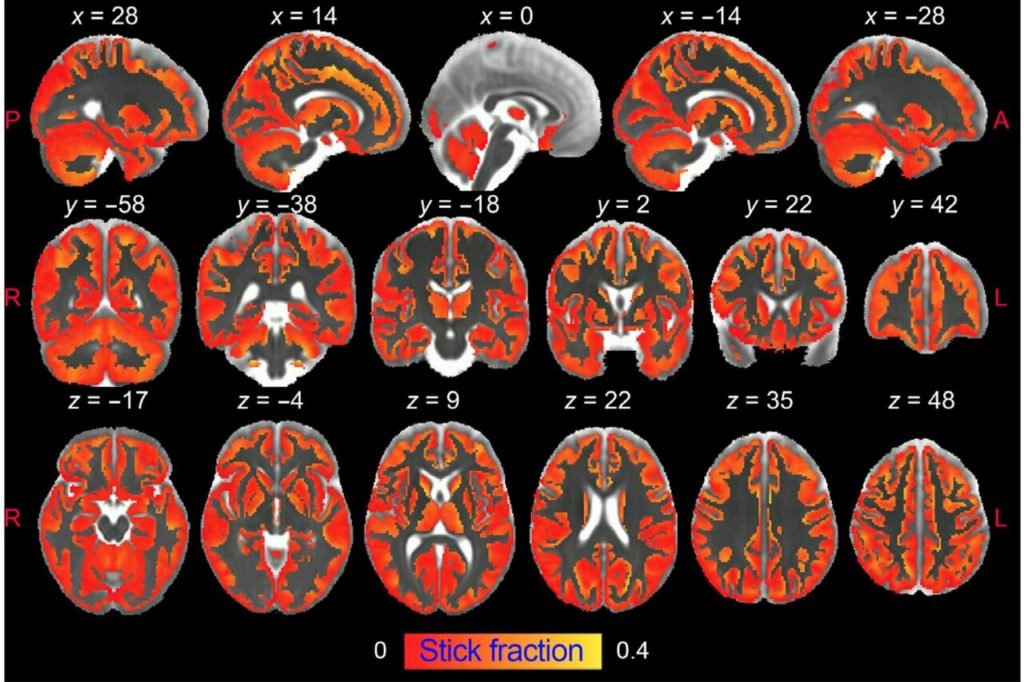

Diante dessas desvantagens, a ressonância magnética ponderada em difusão tem a capacidade única de visualizar a microestrutura cerebral in vivo de forma não invasiva e com alta resolução, capturando o movimento aleatório das moléculas de água no parênquima cerebral para gerar contraste nas imagens de ressonância magnética.

Neste estudo, pesquisadores do Instituto de Neurociências UMH-CSIC desenvolveram uma estratégia inovadora que permite imagens de ativação microglial e astrócitos na substância cinzenta do cérebro usando ressonância magnética ponderada em difusão (dw-MRI).

Silvia de Santis diz que este trabalho também demonstra o valor translacional da abordagem usada em uma coorte de humanos saudáveis em alta resolução, “na qual realizamos uma análise de reprodutibilidade. Acreditamos que caracterizar, usando esta técnica, aspectos relevantes da microestrutura do tecido durante a inflamação, de forma não invasiva e longitudinal, podem ter um grande impacto em nossa compreensão da fisiopatologia de muitas condições cerebrais e pode transformar a prática diagnóstica atual e estratégias de monitoramento de tratamento para doenças neurodegenerativas”.